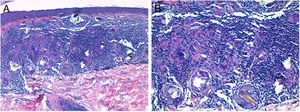

El estudio histopatológico de una de las lesiones de rodilla izquierda mostró en dermis superficial un infiltrado granulomatoso no necrosante constituido por histiocitos epitelioides y células gigantes multinucleadas que fagocitan un material cristalino birrefringente bajo microscopio de luz polarizada (fig. 3). Se estableció el diagnóstico de sarcoidosis papulosa de las rodillas inducida por la terapia antiviral.